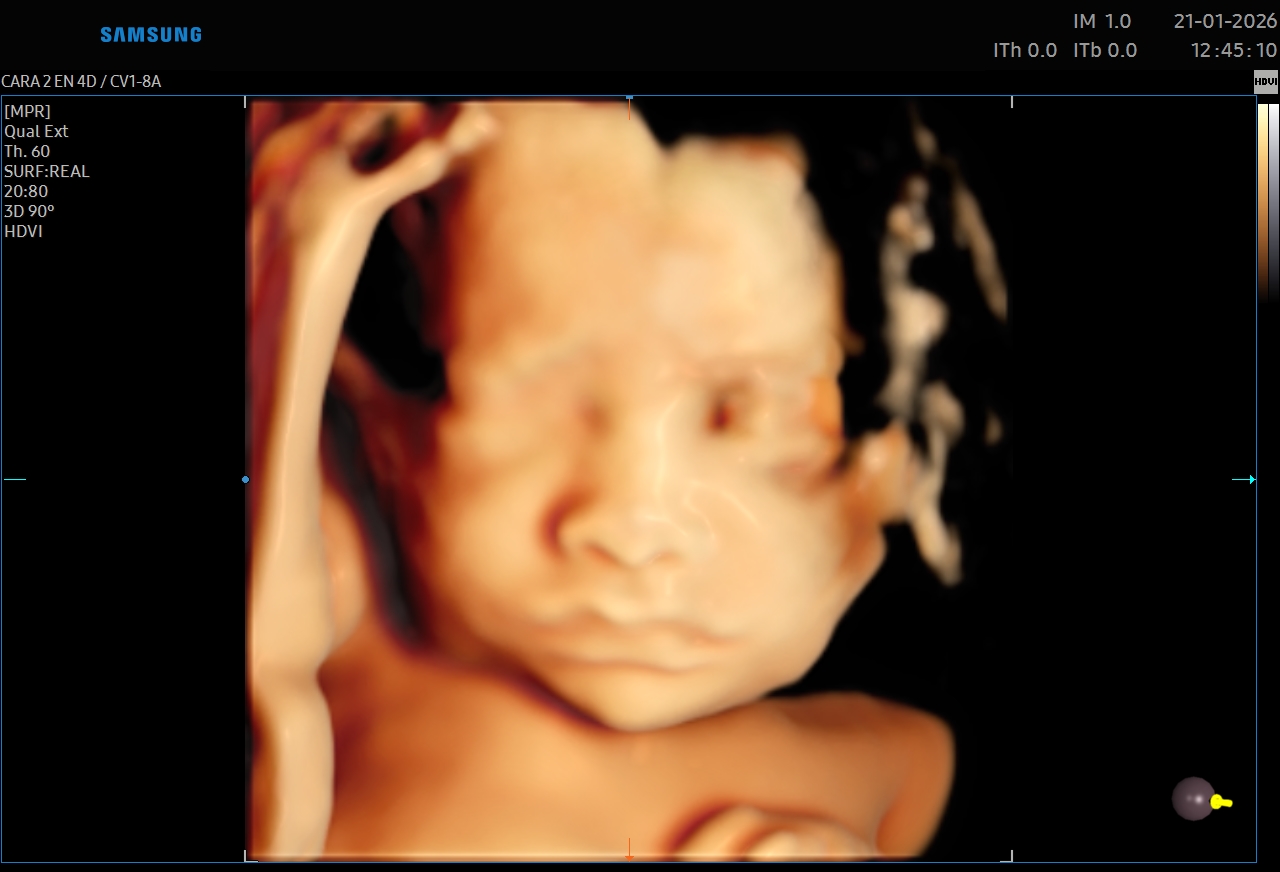

Ecografías 5D

La ecografía 5D es una experiencia única que te permite ver a tu bebé con un nivel de realismo sorprendente, capturando detalles como sus gestos, expresiones y movimientos en tiempo real.

Gracias a esta tecnología avanzada, podrás observar el rostro de tu bebé con mayor claridad, creando un vínculo emocional aún más especial antes de su nacimiento. Es el momento perfecto para compartir con tu familia y guardar recuerdos inolvidables de esta etapa tan importante.

Además de ser una experiencia hermosa, este estudio se realiza con equipos de alta tecnología y bajo supervisión médica, garantizando seguridad tanto para la mamá como para el bebé.